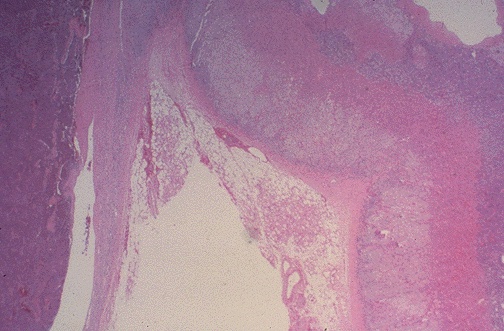

Image 4.4

Describe the histologic findings at low power magnification.